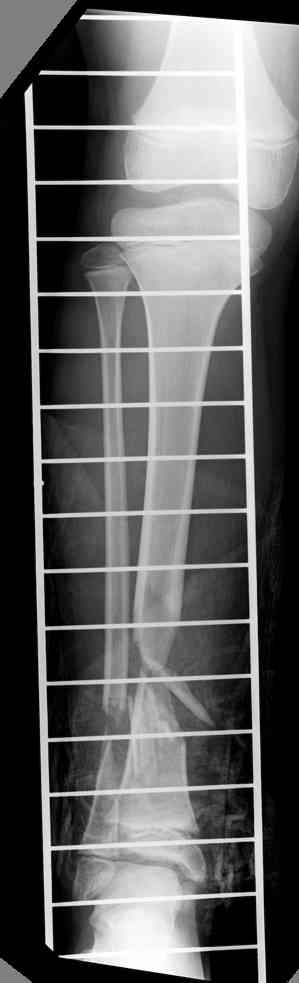

-->> дистальный фрагмент слишком короткий, меньше 2 см, нет места для интрамедуллярного штифта, в отличии от пациента Др. Иванова (прекрастный результат!).

Another choice is simply perform shortening + posterior angulation with Ilizarov or TSF , than gradual correction of the angulation.After all apply third ring on the proximal tibia and start lengthening.

We had recently similar case in 14 years old boy with 45 mm bone defect after open tibial fracture.Boy doing excellent .This technique is not new, Sasha Lerner did it in Rambam , Rozbruch wrote also.

Another advantage of this techniqe is relaxation of soft tissue and possibility for closure even large defects of the skin.In your case I will apply ring on the foot and mid diaphysis of the tibia ,removal of the fibular plate,sindesmotic wire, and after correction of angulation on the proximal tibia.

> Another choice is simply perform shortening + posterior angulation

> with Ilizarov or TSF , than gradual correction of the angulation.

Действительно, если есть длинная косая линия на проксимальном отломке, это жалко будет не использовать. Можно сделать коррекцию угла не обратным разведением фрагментов, а оставить их в контакте, и сделать кортикотомию проксимальнее на 2-3 см. Можно и сейчас отсечь такой фрагмент и транспортировать его с разворотом. Наверно, вариант с ангуляцией более технологичен.

Да, надо удалить все железо, сделать для ангуляции остеотомию малоберцовой на уровне дефеормации, а после восстановления оси сразу освободить стопу. То есть в дистальном отломке tibia надо побольше

спиц с упорами, а на диафизе только half-pins с передне-внутренней стороны, чтобы как можно меньше пострадала передняя группа мышц.